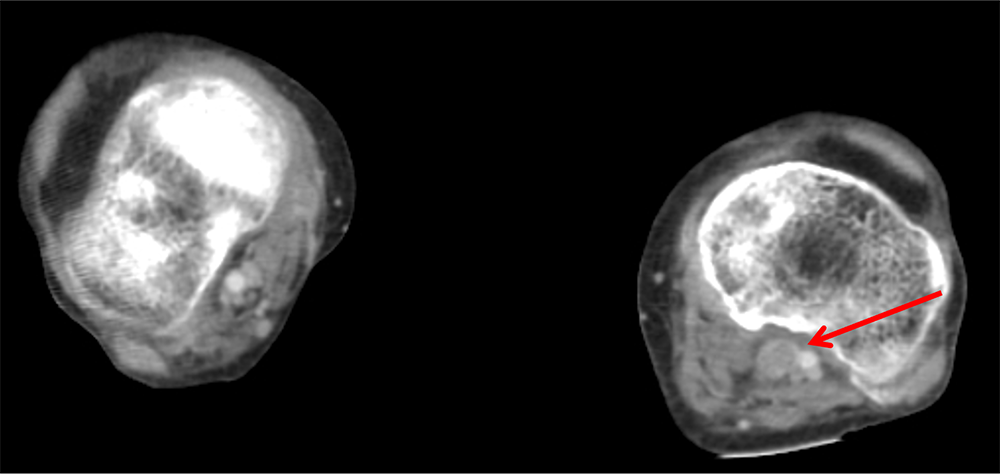

図4.図3と同部位のヨード密度画像

左膝窩静脈内の大部分は筋肉と同程度の青色を示し、造影効果の低下を示している。周囲にわずかに緑色を示す領域が認められる。図3を見直すと、周囲にわずかの造影効果が疑われる。右側の静脈は緑色を示し、造影効果があることを示している。